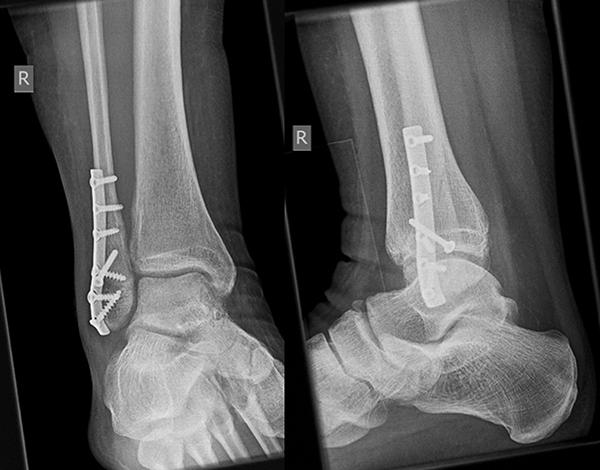

Die Versorgung von AO 44-B Frakturen erfolgt über einen längsverlaufenden lateralen Zugang. In der Regel gelingt eine suffiziente Stabilisierung mittels interfragmentärer Zugschraube (bei langem Frakturverlauf ggf. 2 Zugschrauben) und einer zusätzlichen Neutralisationsplatte (Abbildung 9 & 10).

Bei multifragmentären Frakturen (AO 44-B2.3) oder bei schlechter Knochenqualität sollte die Versorgung mittels winkelstabiler Plattenosteosynthese erwogen werden (Abbildung 11 & 12).